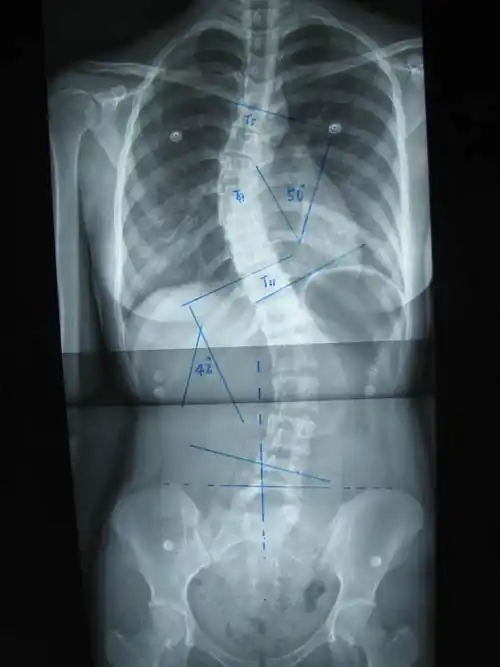

后路手术矫形治疗青少年特发性脊柱侧凸畸形附图片资料